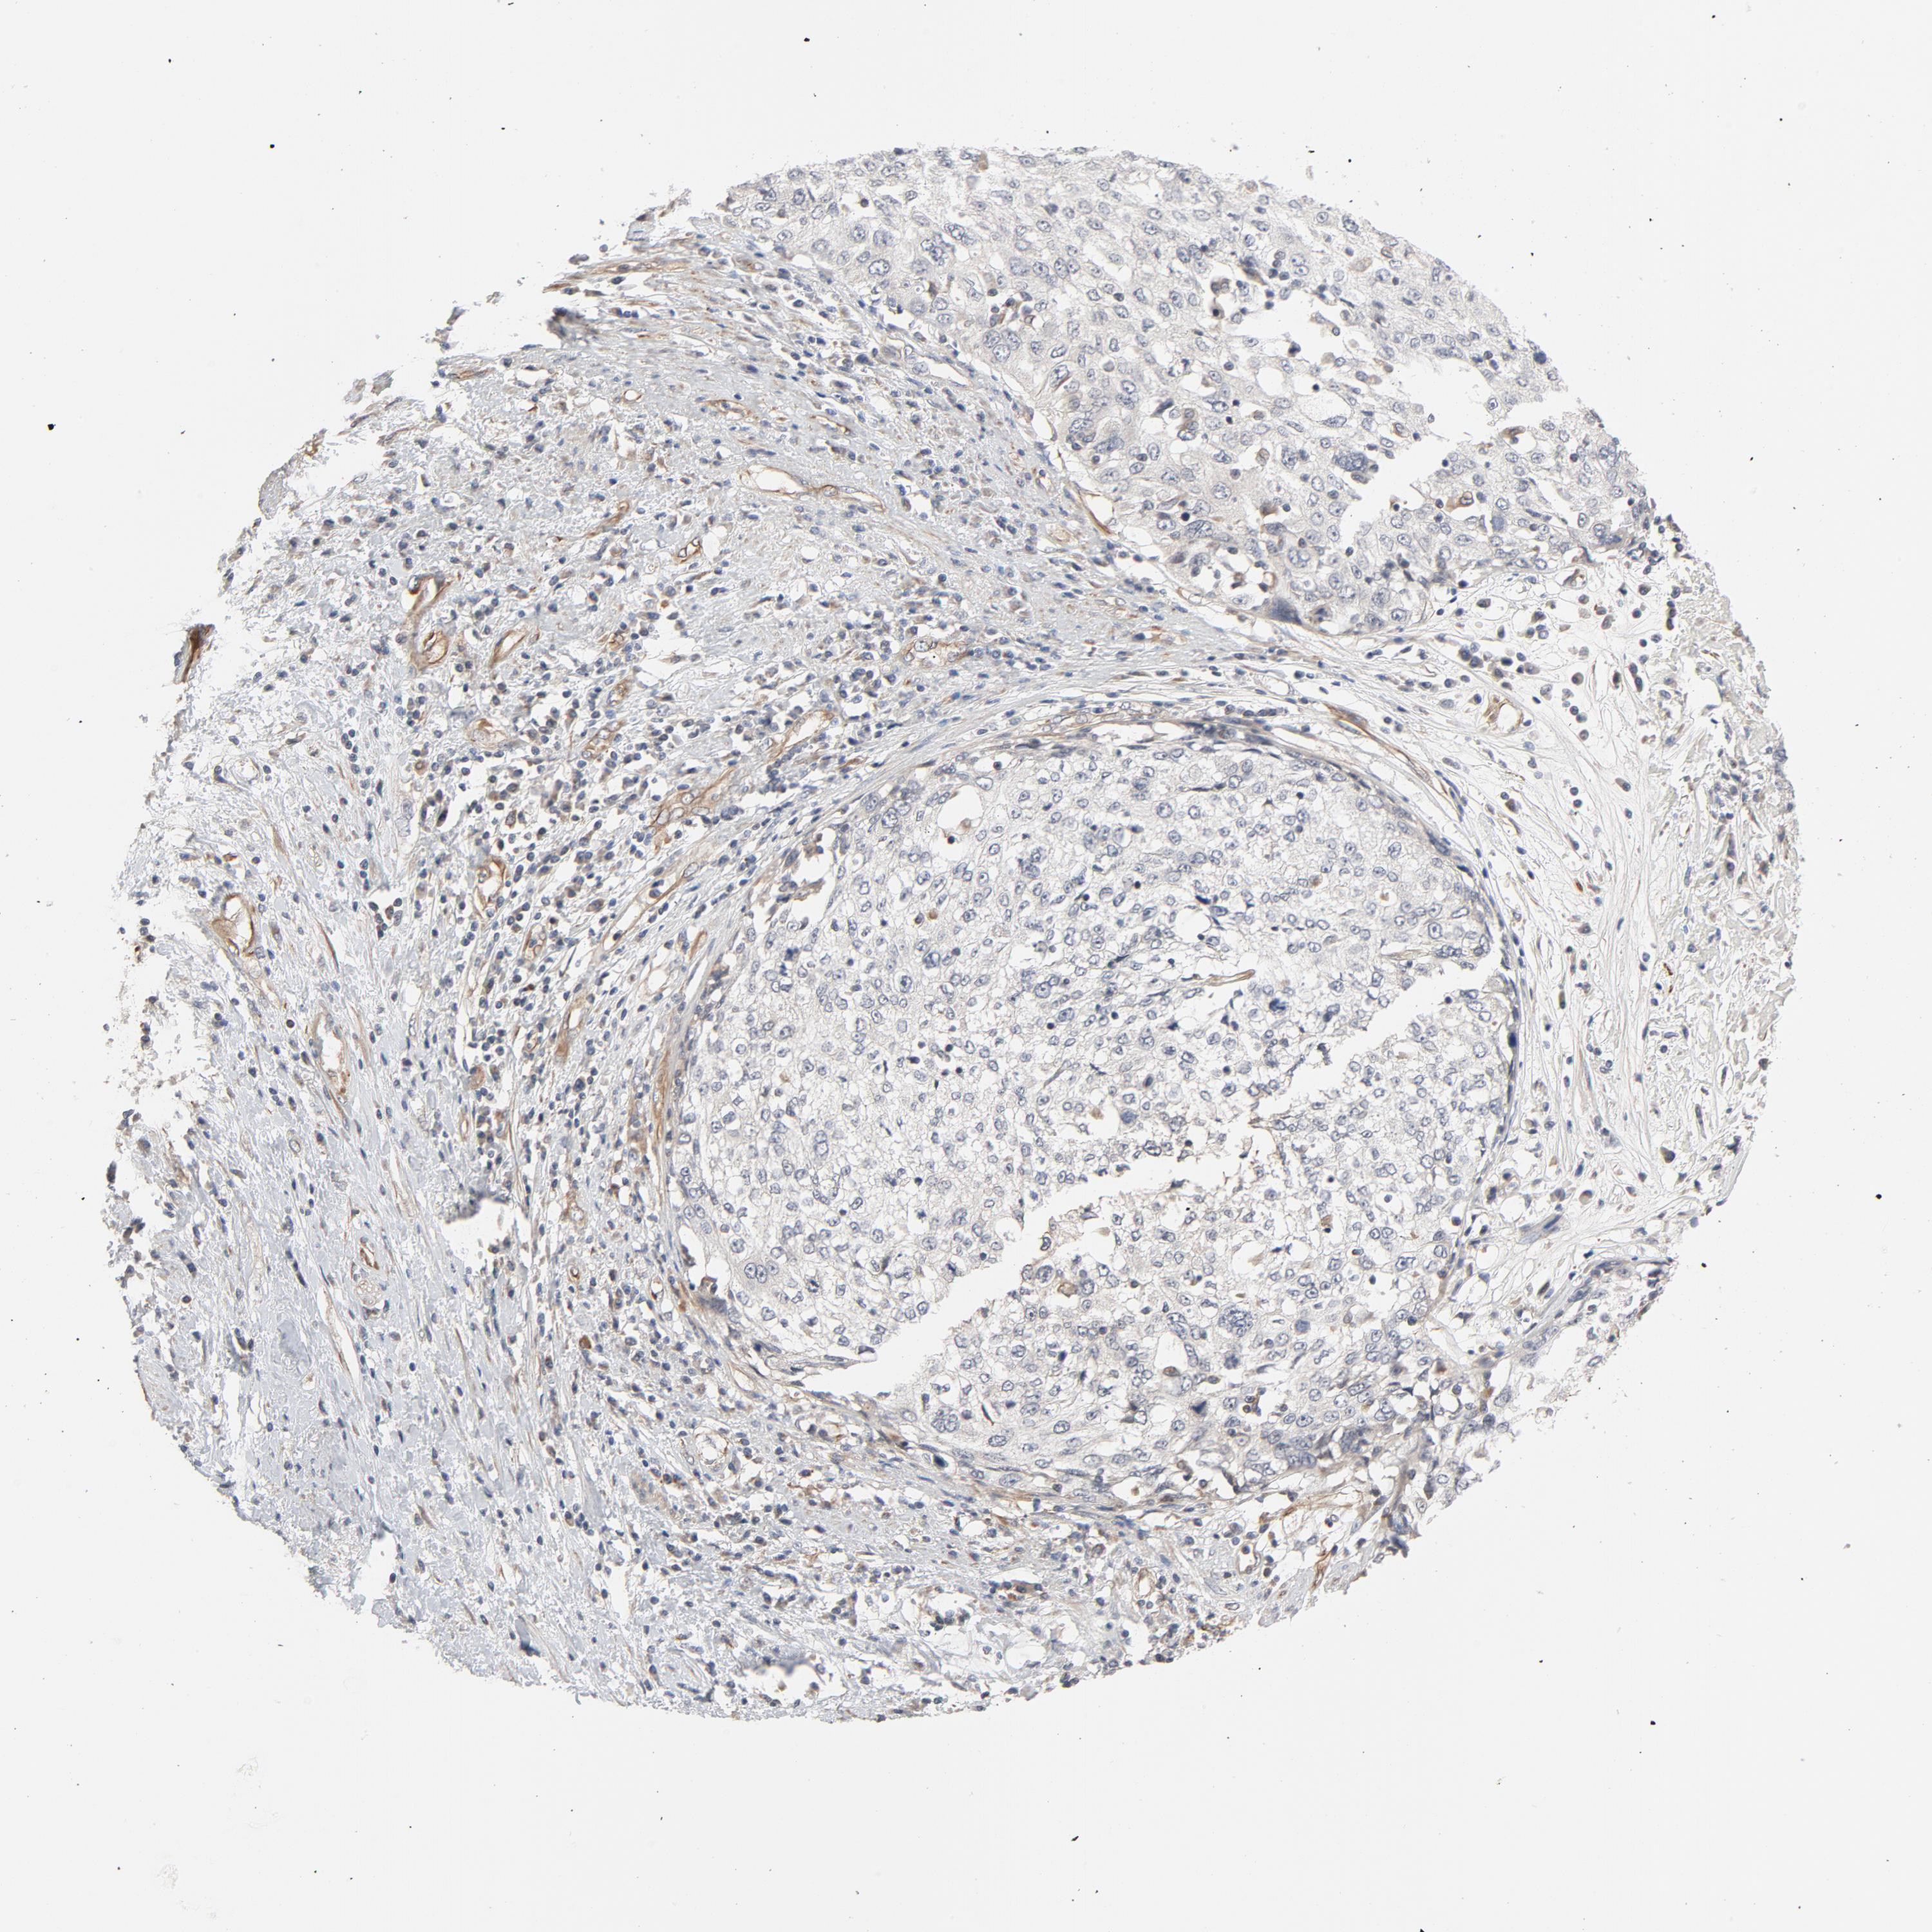

CERVICAL CANCER - Protein expressioni

A mouse-over function shows sample information and annotation data. Click on an image to view it in a full screen mode. Samples can be filtered based on level of antibody staining by selecting one or several of the following categories: high, medium, low and not detected. The assay and annotation is described here.

Note that samples used for immunohistochemistry by the Human Protein Atlas do not correspond to samples in the TCGA dataset.

Antibody stainingi

Antibody staining in the annotated cell types in the current human tissue is reported as not detected, low, medium, or high, based on conventional immunohistochemistry profiling in selected tissues. This score is based on the combination of the staining intensity and fraction of stained cells.

Each image is clickable and will lead to virtual microscopy that enables deeper exploration of all samples and also displays staining intensity scores, fraction scores and subcellular localization as well as patient and tissue information for each sample.

Antibody HPA003747

Antibody HPA019769

Squamous cell carcinoma, NOS